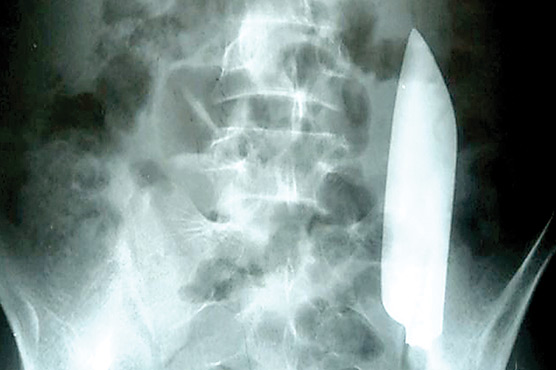

کٹھمنڈو(نیٹ نیوز)نیپال میں ایک دلخراش واقعہ پیش آیا ہے جہاں ایک نوجوان کے پیٹ سے چاقو برآمد ہوا ہے ۔امریکہ کی نیوز ویب سائٹ ‘نیوز وِیک’ کے مطابق یہ واقعہ نیپال میں پیش آیا جہاں 22 برس کا نوجوان پیٹ کے درد کی شکایت لے کر ہسپتال گیا۔۔

اور آپریشن کرنے پر اُس کے پیٹ سے 15 سینٹی میٹر لمبے چاقو کا بلیڈ نکالا گیا۔اس نوجوان کی ہسپتال جانے سے ایک دن قبل کسی سے لڑائی ہوئی تھی جس کے بعد مقامی ہیلتھ کیئر ورکر نے جسم پر آنے والوں زخم پر ٹانکے لگائے تاہم اس بارے میں کسی کو بھی شک نہیں ہوا کہ اِس نوجوان کے پیٹ میں چاقو موجود ہے ۔مقامی ہیلتھ ورکر نے نوجوان کے ٹانکے لگانے کے بعد اُسے گھر بھیج دیا۔یہاں دلچسپ بات یہ ہے کہ اس نوجوان کو بھی لڑائی کے واقعے کے بارے میں واضح علم نہیں تھا کیونکہ جب یہ واقعہ ہوا تو اُس وقت وہ شراب کے نشے میں دھت تھا۔